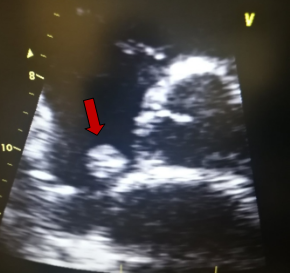

Τα μυξώματα είναι τα πιο κοινά καλοήθη νεοπλάσματα της καρδιάς σε ενήλικες. Το μύξωμα είναι μια ενδοκοιλοτική μάζα, συνήθως διαμέτρου 4 – 8 cm. Στις περισσότερες περιπτώσεις βρίσκεται στον αριστερό κόλπο (75%), και συνδέεται με το μεσοκολπικό διάφραγμα, πάνω από τον ωοειδή βόθρο (=το μεσαίο λεπτότερο τμήμα του μεσοκολπικού διαφράγματος). Πιο σπάνια ένα μύξωμα βρίσκεται στο δεξιό κόλπο και ακόμη πιο σπάνια στις κοιλίες. Τα περισσότερα μυξώματα είναι σποραδικά (> 90%) και σπάνια υποτροπιάζουν μετά από πλήρη εκτομή. Τα πολλαπλά μυξώματα (συγχρόνως, διαδοχικά ή υποτροπιάζοντα) αποτελούν ένα χαρακτηριστικό των συνδρόμων μυξώματος (που αντιπροσωπεύουν το 7% των περιπτώσεων καρδιακού μυξώματος). Αυτές οι περιπτώσεις είναι οικογενείς, ως εκδήλωση του σπάνιου συνδρόμου Carney, το οποίο είναι ένας συνδυασμός καρδιακών και δερματικών μυξωμάτων, ενδοκρινικών διαταραχών (αδενωμάτων της υπόφυσης, διαταραχών του φλοιού των επινεφριδίων ή όγκων των όρχεων) και δερματικής εφηλίδωσης (Η εφηλίδωση είναι η παρουσία πολλαπλών εφηλίδων, δηλαδή μικρών χρωστικών κηλίδων στο δέρμα που είναι σαφώς αφοριζόμενες, λόγω μιας καλοήθους υπερπλασίας των μελανοκυττάρων που είναι γραμμική στην εξάπλωσή της).

Στην ηχοκαρδιογραφία, το μύξωμα έχει την εμφάνιση μίας ανομοιογενούς κινητής μάζας, συχνά περίπου σφαιρικής, διαμέτρου συνήθως 4-8 cm, με λεία ή με λοβωτή (που φέρει μικρά τόξα στο περίγραμμά της) επιφάνεια. Η μάζα είναι προσαρτημένη στην ενδοκαρδιακή επιφάνεια (συνήθως στο μεσοκολπικό διάφραγμα) με στενή βάση, δηλαδή μίσχο. Σε κάποιες περιπτώσεις μπορεί να συνδέεται στο μεσοκολπικό διάφραγμα με ευρεία βάση. Η ηχογένεια τους δεν είναι ομοιογενής και μπορεί να περιλαμβάνουν υπόηχες περιοχές και σε κάποιες περιπτώσεις ασβεστώσεις. Τα πολυποειδή μυξώματα είναι μεγαλύτερα με λεία επιφάνεια και περιλαμβάνουν υπόηχες και κυστικές περιοχές λόγω εστιών αιμορραγίας και νέκρωσης εντός του όγκου . Τα θηλοειδή μυξώματα τείνουν να είναι μικρότερα και έχουν πολλαπλές λαχνοειδείς προσεκβολές. Αυτός ο υποτύπος σχετίζεται με εμβολικά φαινόμενα. Η θεραπεία ενός καρδιακού μυξώματος είναι η ριζική (πλήρης) χειρουργική αφαίρεση του όγκου.